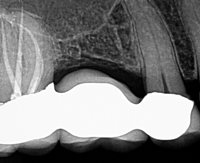

The patient presented with a referral for root canal treatment of tooth #3. Pulp vitality testing indicated that #3 was vital, while #2 was necrotic. CBCT revealed that a large area of low density was associated with #2 and was encroaching on #3, therefore giving the appearance that #3 may also need root canal treatment. The patient and I agreed that incision and drainage, along with root canal treatment of #2, was the best first-line treatment.

Tooth #2 had 4 calcified, necrotic canals. The

EndoPilot and

Procodile Q™ files were instrumental in completing this case safely and efficiently in a single visit. The Ultrasonic attachment on the EndoPilot was critical for accessing the MB2, especially in this area of the mouth where access can be a challenge!